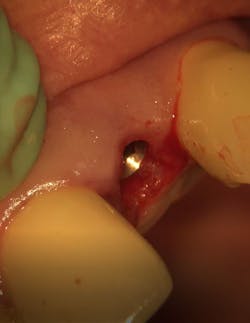

Case report: Extraction/immediate implant placement with provisional, using the Ditron Ultimate Implant System

- Chief complaint: Fracture of clinical crown tooth no. 10

- Radiographic findings: Fractured lateral incisor with periapical pathology

- Clinical findings: Oblique fracture no. 10 to bone level

- Diagnosis: Unrestorable maxillary lateral incisor

- Treatment plan: Extraction/immediate implant placement with nonfunctional provisional

- Implant: Ditron Ultimate 3.75 x 16 mm

- Abutment: Final straight 11.5 mm titanium abutment delivered at time of implant placement